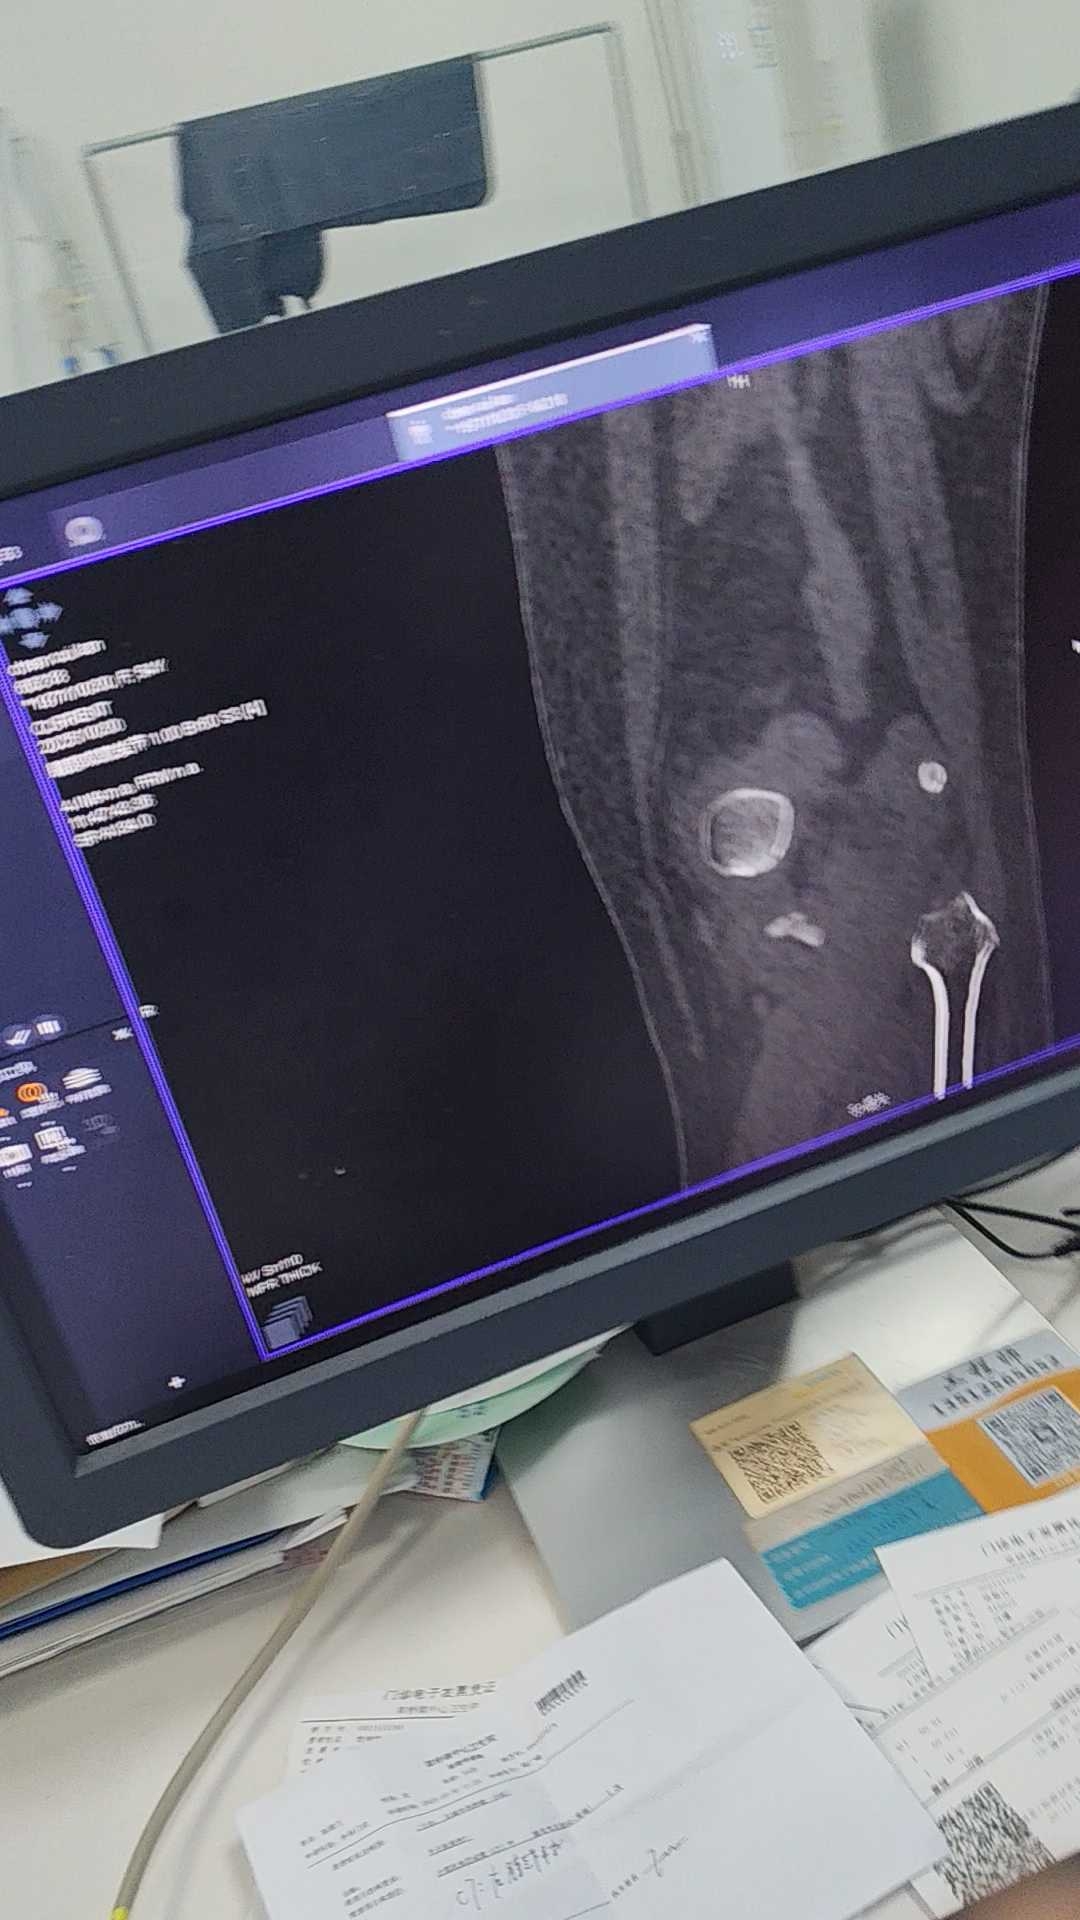

患者,女,54岁,外伤后左膝肿痛活动受限2小时,CT片如下

各位主任看看需要手术吗?